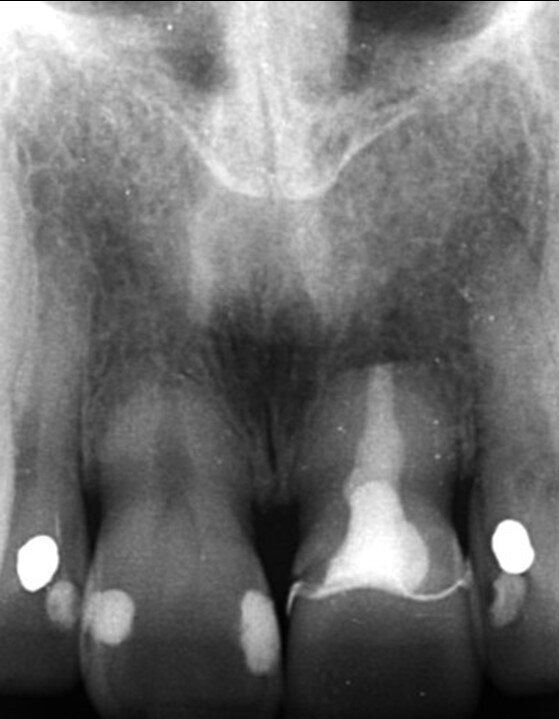

Una paziente di 53 anni si è presentata in studio con un incisivo sinistro fratturato a cui era stata più volte cementata una corona di ceramica (Figg. 1, 2). L’anamnesi e gli esami hanno evidenziato una buona salute sistemica e orale, un’occlusione ben equilibrata e nessuna abitudine al fumo. La tomografia cone beam (CBCT) e la radiografia periapicale hanno mostrato un riassorbimento radicolare esterno con inserimento nell’osso alveolare molto scarso, insufficiente per un adeguato posizionamento di un comune perno endocanalare (Figg. 3, 4). Considerando che il dente fratturato si trovava nella zona estetica, il paziente richiese un restauro nel modo più sicuro e più veloce possibile.

Fig. 3_Radiografia periapicale pre-operatoria.

Fig. 4_Scansione CBCT pre-operatoria.